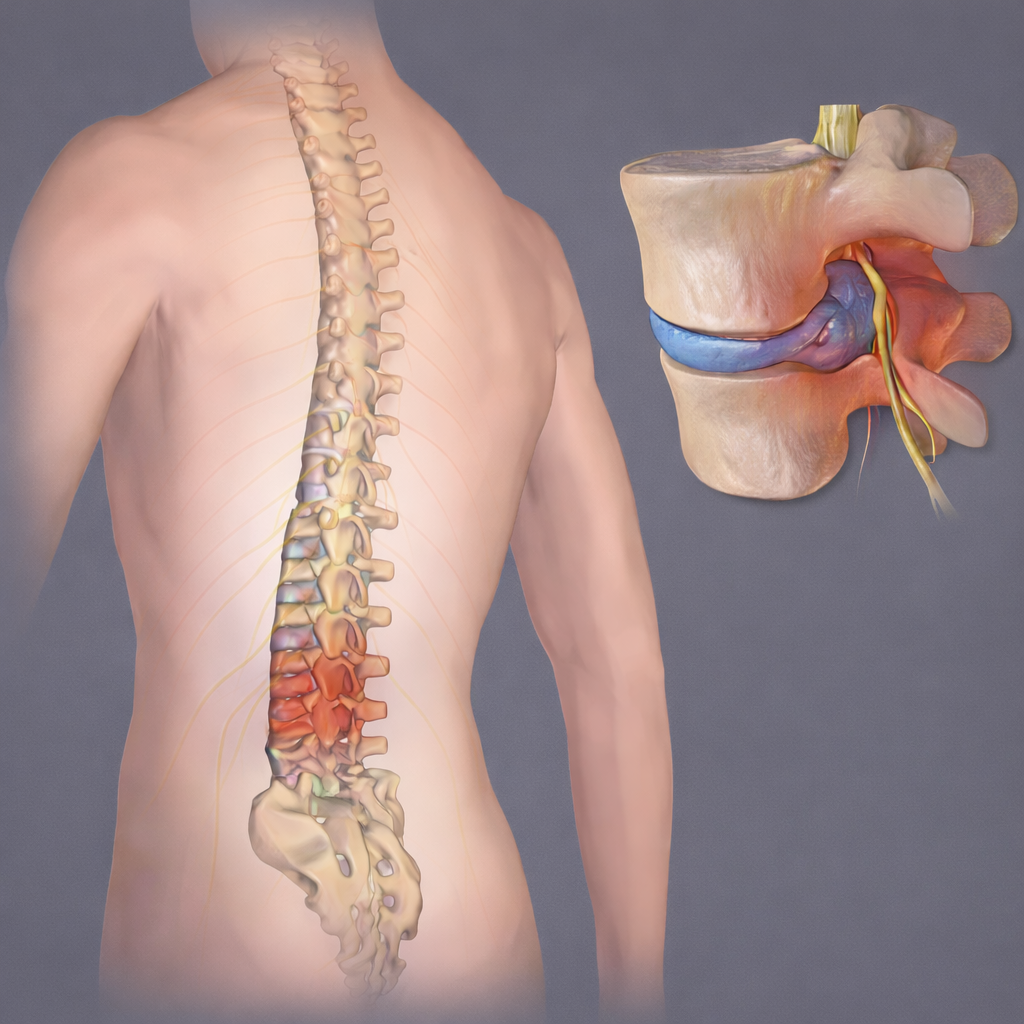

Management of disc-related pain through medications, physiotherapy, lifestyle guidance, or surgical intervention when necessary.

Evaluation and treatment of neck and lower back conditions affecting nerves, movement, and posture.

Personalized spine treatment options including conservative care and surgery based on condition severity.